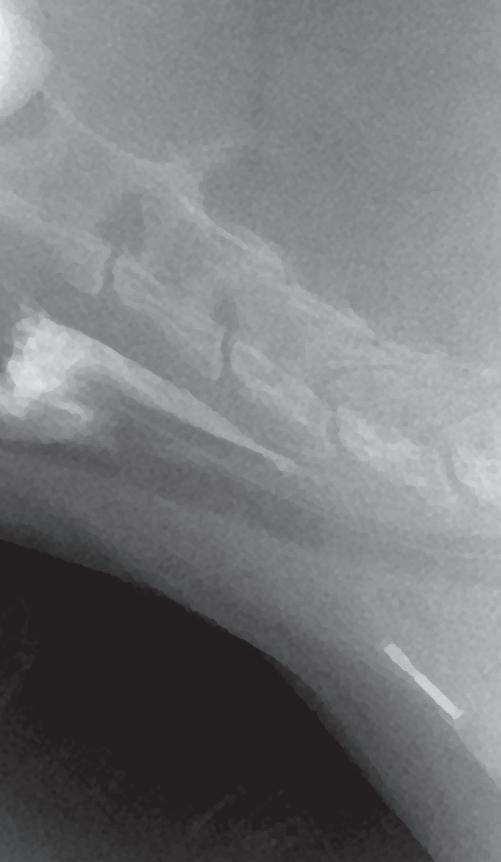

Se realiza ecocardiografía en la cual observamos engrosamiento de la válvula mitral (Fig. 2) y alteración de la estructura de las cámaras cardiacas: ratio atrio izquierdo/aorta 2,25 (Fig. 3), diámetro de ventrículo izquierdo en diástole normalizado (DVIdn) 1,98, patrón de flujo transmitral pseudonormal con velocidad máxima de onda E de 1,7 m/s, tiempo de relajación

isovolumétrica (TRIV) acortado, 30 ms, y regurgitación mitral de hasta 4,6 m/s. En la ecocardiografía se observa también una masa hiperecoica bien definida de hasta 7 x 4,3 cm de diámetro en la base aórtica (Fig. 4) y un acúmulo de derrame pericárdico leve que no permite la pericardiocentesis. Además, se detecta un nódulo hiperecoico redondeado de 1,56 cm de diámetro en la válvula tricúspide (Fig. 5).

Figura 2. Ecocardiografía en corte paraesternal izquierdo eje largo, de 4 cámaras en la que se observa engrosamiento de la válvula mitral (flecha). Figura 3. Ecocardiografía en corte paraesternal derecho eje corto en base de corazón, visualizando ratio atrio izquierdo/aorta aumentado. Figura 4. Ecocardiografía en corte paraesternal izquierdo en base de corazón, en las que se observa la estructura hiperecoica y heterogénea junto a la aorta en un corte de la lesión transversal (A) y otro longitudinal (B). Compatible con neoplasia. A B Figura 5. Ecocardiografía en corte paraesternal izquierdo eje largo, optimizada para válvula tricúspide en la que se observa estructura hiperecoica.

La ecocardiografía es el método de elección para confirmar el diagnóstico de EDVM y estimar la severidad de la regurgitación mitral. Los hallazgos ecocardiográficos incluyen el engrosamiento y/o prolapso de las hojas mitrales junto con la identificación de la regurgitación mediante Doppler. Como se comprobó en el estudio post mortem en nuestro caso, a menudo se observan alteraciones en la válvula tricúspide, pero suelen ser menos marcadas que las de la válvula mitral.2 La ecocardiografía permite adquirir dimensiones del AI en relación con la aorta, o valoración del diámetro del VI en diástole y sístole, muy útiles para estimar el grado de remodelación (agrandamiento) cardíaco.2